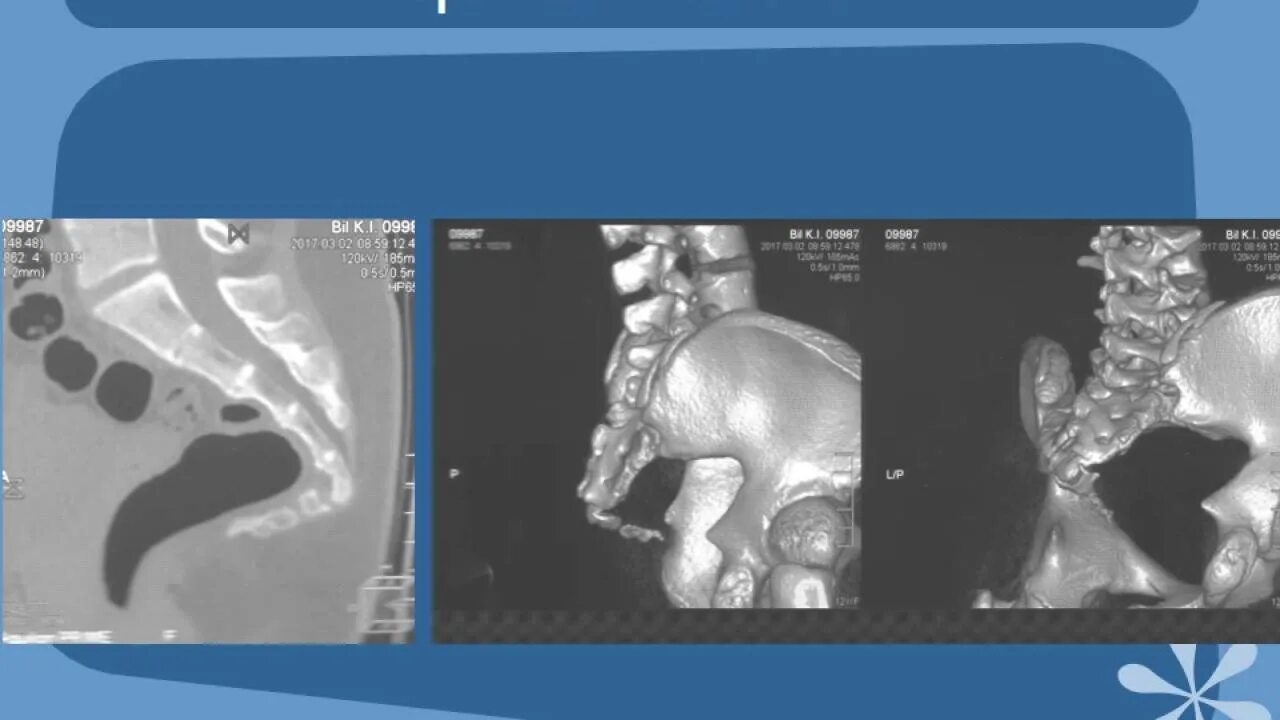

Кт крестцово-копчикового отдела позвоночника. кт пояснично-крестцового отдела позвоночника. кт крестцового отдела позвоночника. кт (мскт) грудного отдела позвоночника.

Позвонки крестца кт. переломы костей таза кт.

Перелом боковых масс крестца кт. перелом 5 крестцового позвонка рентген. перелом латеральной части крестца. перелом поперечного отростка l5 рентген.